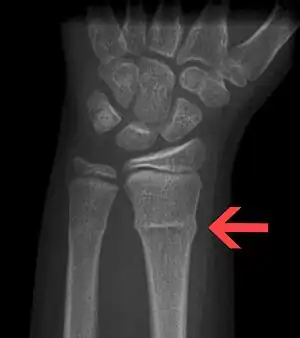

X-ray of a torus fracture involving the distal radius

Torus fracture, also known as a buckle fracture, is a type of broken bone that generally occurs in children in which the outer aspect only buckles rather than fully breaks.[2][3] Symptoms generally include pain to the affected area.[1] Associated injuries may include plastic deformation.[3]

It typically results from a fall onto an outstretched hand.[1] Though other causes may include non-accidental injury.[3] The distal forearm is most often affected; though, it may also involve the ribs.[1][2] Diagnosis is generally by X-ray.[1]

Buckle fractures can generally be identified by X-ray. The diagnosis is made from both anterior/posterior and lateral projections. The typical features include:

• The buckling of cortical bone, which may appear as a small bulge or protuberance in the radius or ulna.

• The bone may have a slight angulation.[9]